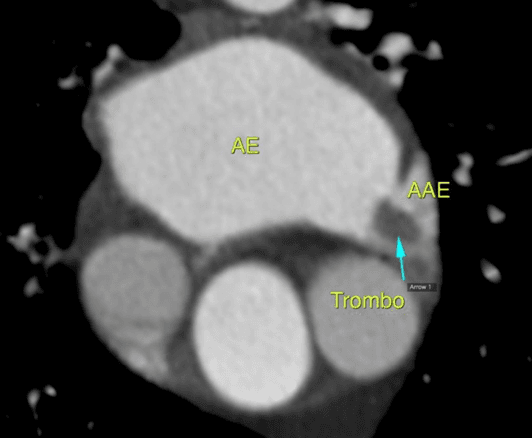

Sabemos que a fibrilação atrial (FA), taquiarritmia sustentada mais comum, está associada a eventos cardioembólicos como o acidente vascular cerebral (AVC). Alguns escores estimam o risco anual de AVC…